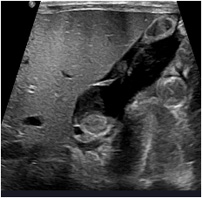

• 간초음파 이상 (지방간, 비장비대, 담석 등)